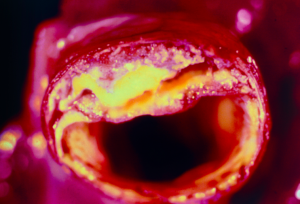

Algunas bacterias intestinales facilitan los depósitos de grasa en las arterias del corazón